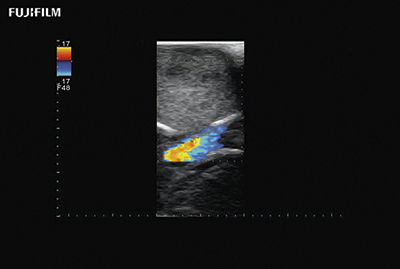

Liver Spectral Doppler using C22I

Curved array deep penetration “I” style finger-grip transducer for open kidney surgical procedures. Allows for palpating organs and scanning at the same time.